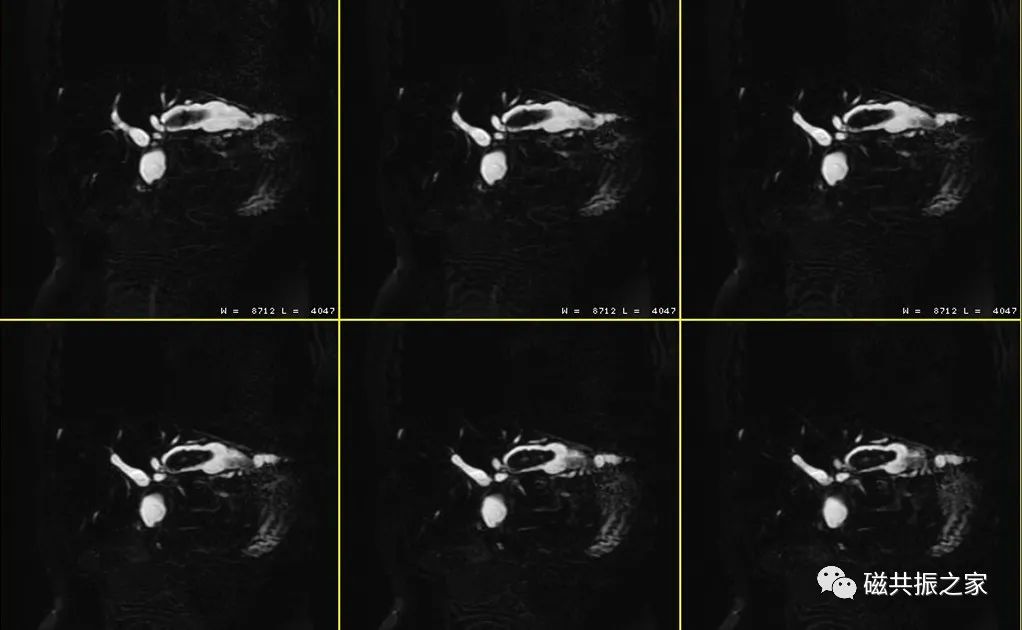

厚模块2D MRCP序列

主要在横轴位上定位,采用厚层模块扫描,采用放射状的定位方式;并在冠状和矢状位上调整FOV的上下位置。